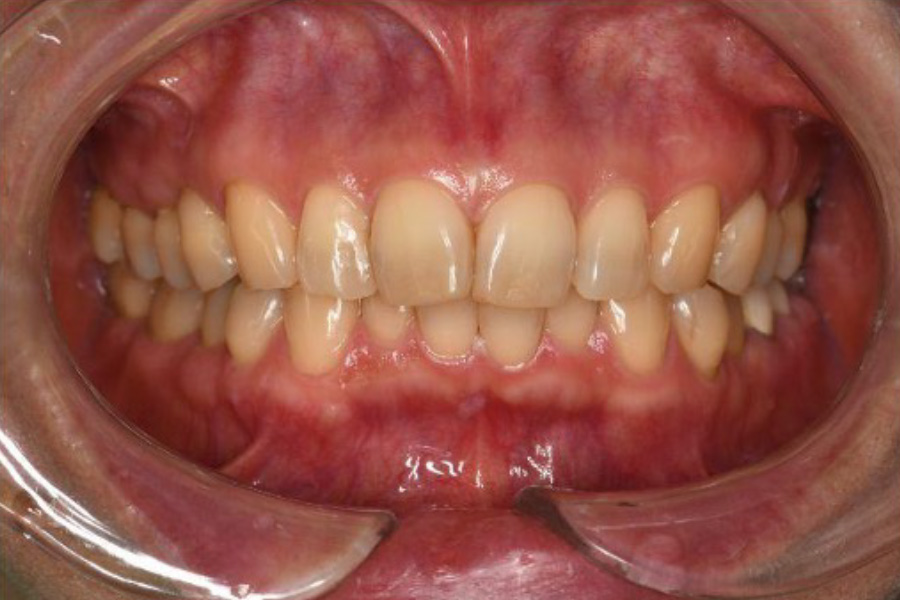

治療後

(義歯未装着)

(義歯装着時)

【口腔内写真】

義歯装着前の口腔内状態(左下)

義歯を外した状態の画像を見ると、治療の初期段階で行った「地盤管理」がいかに成功したかが一目でわかります。

通常、抜歯後の「地盤(歯ぐきや骨)」は時間とともに痩せ、大きく窪んでしまいます。しかし、本症例では戦略的抜歯と同時にリッジプリザベーション(歯槽骨保存術)を施したことで、欠損部の歯槽堤(歯ぐきの盛り上がり)が見事に保存されています。

その高さは、隣接する健康な歯(4番・5番)の歯頸ライン(歯ぐきとの境目)とほぼ同じレベルに維持されています。この平坦で強固な「プラットフォーム」が完成しているからこそ、その上に載る精密な金属床義歯は、ガタつくことなく強力な「噛む力」をしっかりと受け止めることができるのです。

【口腔内写真】義歯装着時の左側観

- 精密金属床義歯とRPIクラスプ:

『力を逃がす』高度なエンジニアリング

左下奥歯の欠損部には、最新の設計に基づいた精密金属床義歯が装着されています。注目すべきは、第二小臼歯にかかっているRPIクラスプの「Iバー」です。

これは、噛む力が加わった際に、支えとなる歯を「ねじる」ような有害な回転力を逃がす特殊な構造です。建築で言えば、地震の揺れを吸収する「免震構造」のような役割を果たし、残された貴重な歯(地盤)の寿命を最大限に延ばします。 - ジルコニアクラウンへの更新: